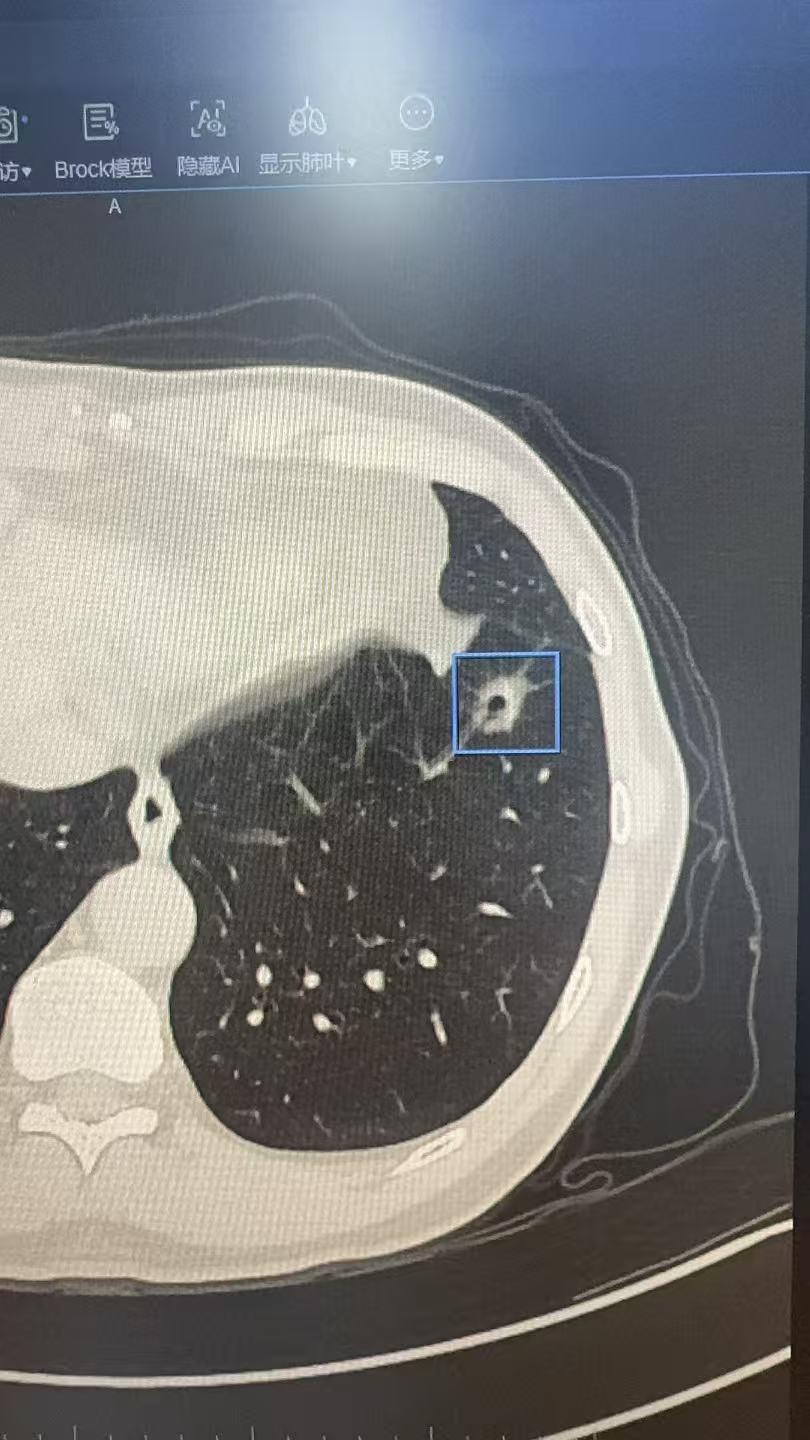

图识肺结节……图识肺结节……可以如图发在评论区,我会抽空回复……

这个8mm的微浸润腺癌,看了很多地方没看出来,我们团队没有漏掉这个恶性...